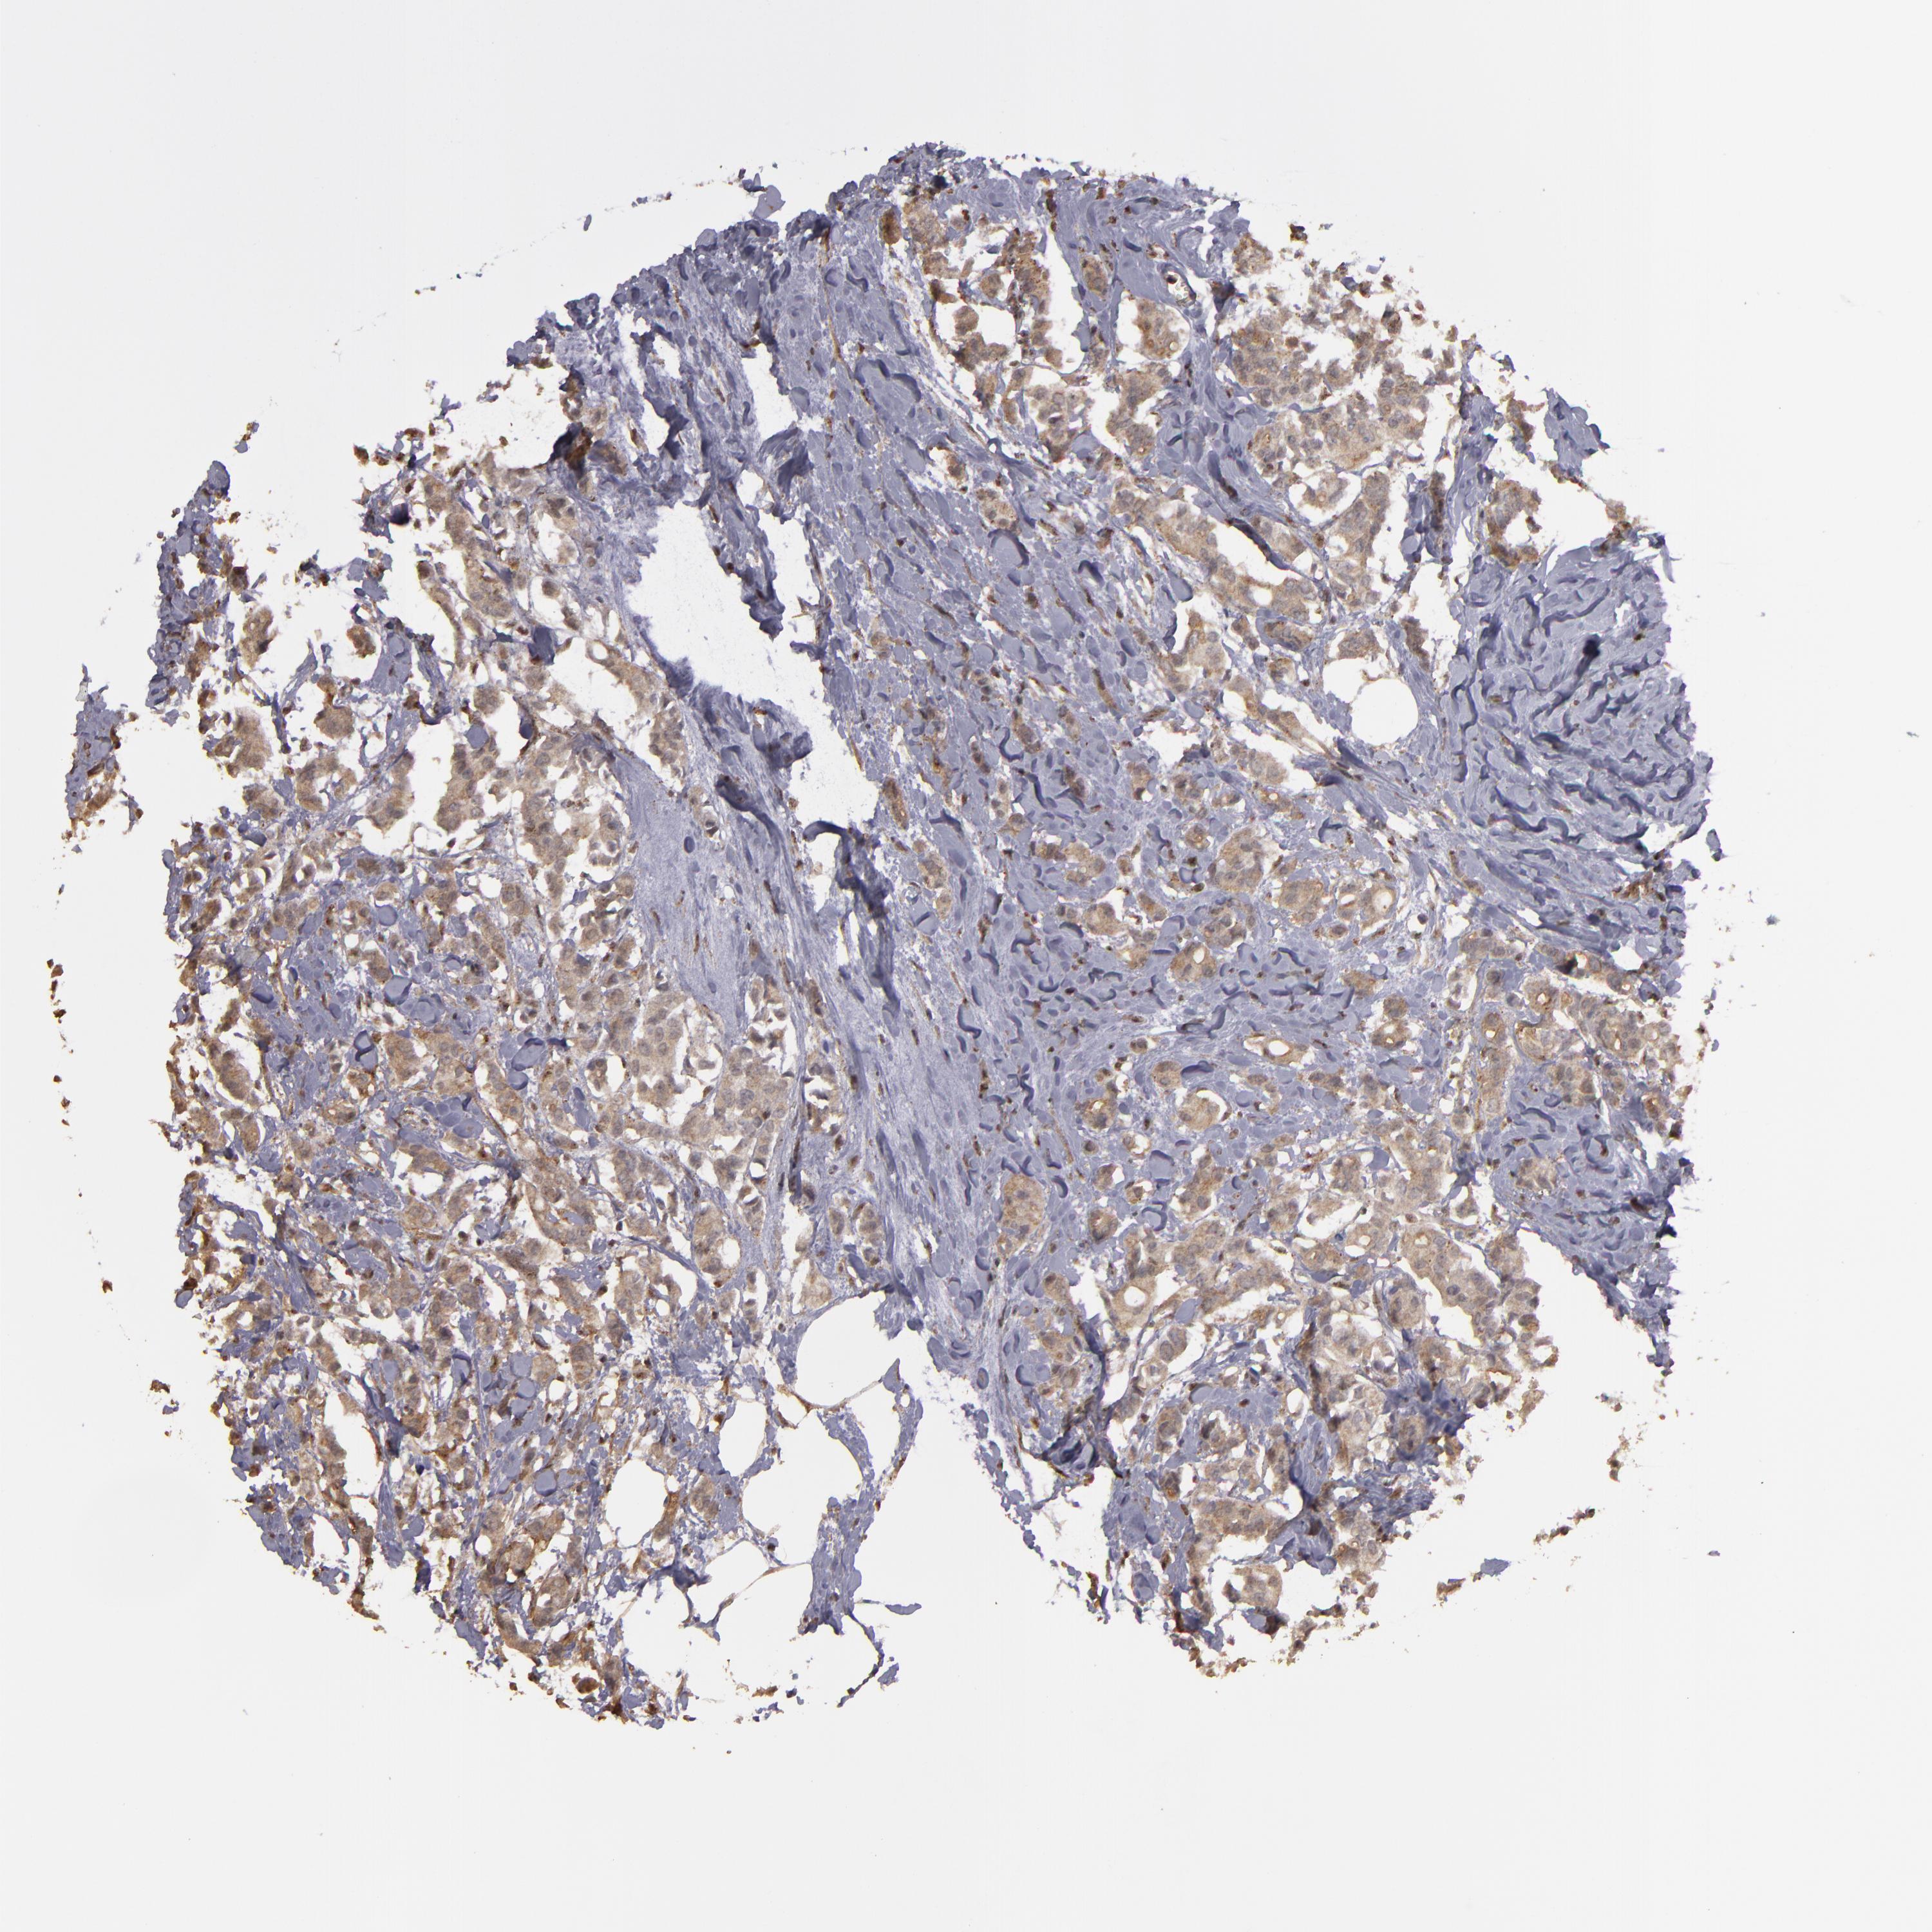

CANCER BREAST CANCER Show tissue menu

BRCA TCGA BRCA VALIDATION PROTEIN EXPRESSION